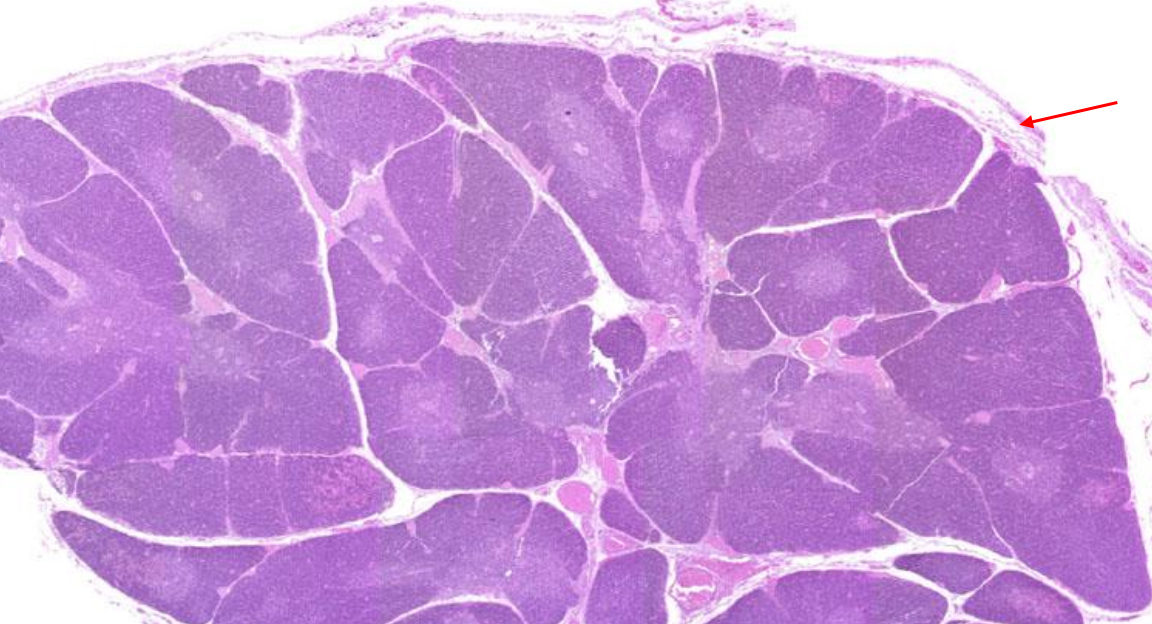

thymic capsule

A connective tissue covering that surrounds the thymus, appearing as a thin, fibrous outer layer that provides structural support and extends inward to form septa that divide the thymus into lobules.

thymic lobules

Each cortex of each lobule exhibits regions of rich purple staining.

What makes up the adult thymus?

It contains 𝐚𝐛𝐮𝐧𝐝𝐚𝐧𝐭 𝐚𝐝𝐢𝐩𝐨𝐜𝐲𝐭𝐞𝐬 (fat cells in the subcutaneous layer in the thymus) and 𝐟𝐢𝐛𝐫𝐨𝐮𝐬 𝐜𝐨𝐧𝐧𝐞𝐜𝐭𝐢𝐯𝐞 𝐭𝐢𝐬𝐬𝐮𝐞 (tissue that forms the thymic capsule)